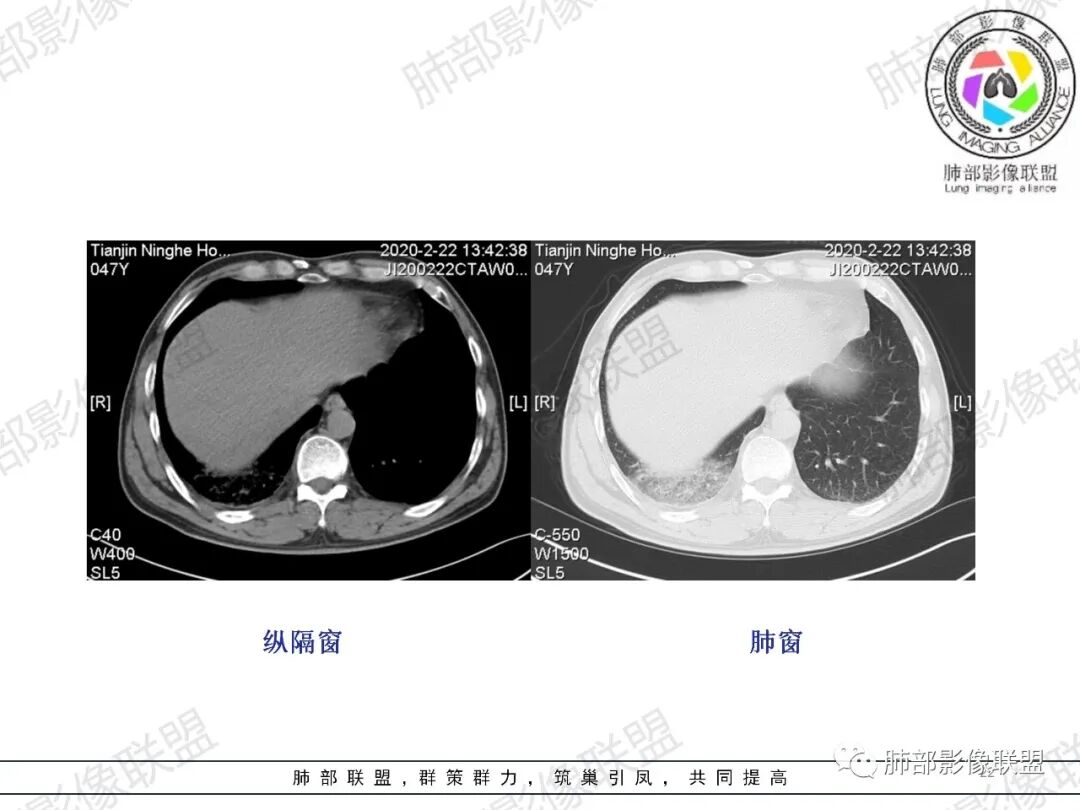

小兜:男,47岁,胸闷气短入院,一天前无明显诱因胸闷气短伴呼吸困难,夜间出现右侧胸痛,与呼吸及体位有关,曾有一次痰中带血。CT示右肺上叶尖段多发结节,条索影,可见树芽征及反晕征。右肺下叶胸膜下片状密度增高影,宽基底与胸膜相连,成扇形。综合考虑右肺上叶尖段结核可能;右肺下叶肺栓塞?病毒性肺炎?

水晶石头:患者中年男性,胸闷、气促1天。伴右胸痛及痰中带血。否认结核、心脏疾病等病史。查体无特殊。完善血常规白细胞计数、中性粒细胞百分比及C反应蛋白升高。心电图、B超、凝血功能、降钙素原、脑钠肽正常。胸部CT:右肺上叶尖段多发结节、斑片、纤维条索影,见小叶间隔增厚及反晕征。右肺下叶后基底段胸膜下片状磨玻璃影,见小叶内间隔增厚。右侧胸膜增厚,未见明显淋巴结增大。综合考虑右上肺结核病变,右下肺肺栓塞。鉴别病毒性肺炎及恶性病变。

然后就是右下叶病灶的问题

后基底段,胸膜下,这个没问题吧

我们看看病变的形态、密度、边缘、内部改变

GGO密度

边缘不清

可惜没有重建,楔形?

细网格明显

支气管通畅,壁增厚

血管增粗

急性肺栓塞发生后,因肺动脉血流阻断而引起供血动脉远端肺组织的坏死称为肺梗死。肺动脉分支一旦血流阻断,远端毛细血管网则因管壁缺氧而通透性增高,液体及红细胞随之渗出,肺泡腔内渗出物增加,必然会影响气体交换,随后肺梗死发生。既往有研究表明,肺外周楔形阴影可以认为是肺梗死的征象,是唯一与肺栓塞显著相关的肺实性异常,该征象在肺栓塞患者中的发生率为25%。